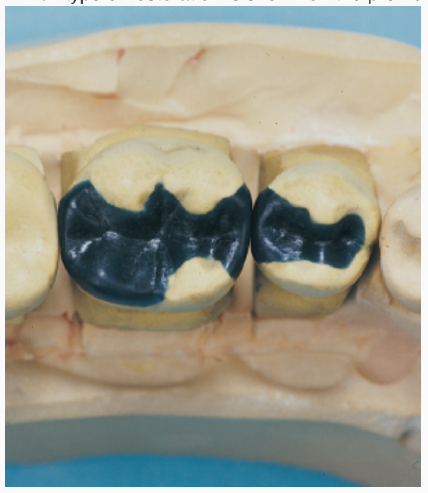

The levels of mutans streptococcus have been shown to be significantly higher in the proximal plaque adjacent to which type of posterior restoration?

Composite resinNDEB released questions part 2 set 1